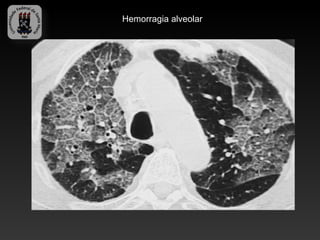

-Hemorragia alveolar (opacidades em vidro fosco com espessamento

septal)

Hemorragia alveolar

DPD 4- Associada a doenças colagenovasculares -LUPUS ERITEMATOSO SISTÊMICO -Mais comumente afeta mulheres jovens -Doença pleuro pulmonar ocorre em mais da metade dos pacientes -Pleurite, pneumonite inflamatória(lúpica), fibrose pulmonar interticial, hipertensão pulmonar, pericardite, disfunção diafragmática, hemorragia alveolar difusa. -Pneumonite lúpica é pontencialmente fatal (opacidades intersticiais, vidro fosco, febre e hipoxemia) -Hemorragia alveolar (opacidades em vidro fosco com espessamento septal)